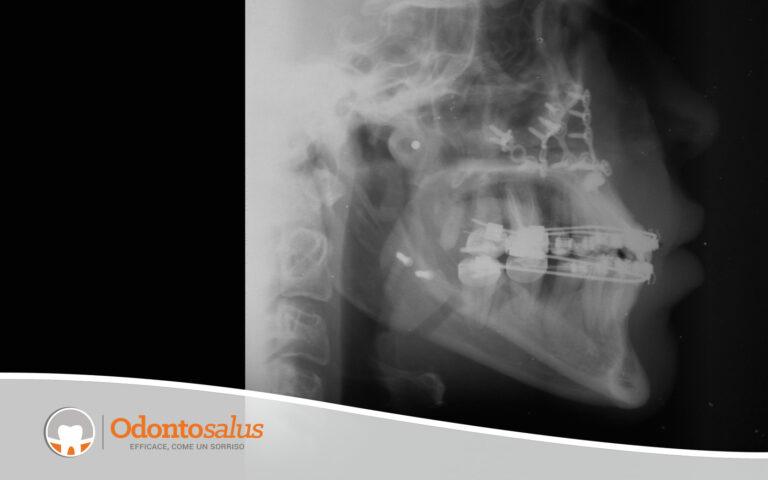

Giovane paziente insoddisfatta del suo profilo estetico, in particolare della parte mediana del suo viso, e con problemi funzionali dovuti ad un mascellare fortemente retruso, come da esame radiografico pre-cure.

Dopo aver effettuato lo studio del caso mediante tracciato ortodontico, è stato predisposto un avanzamento del mascellare superiore, associato ad un lieve arretramento e alla rotazione della mandibola, al fine di migliorare l’estetica e la funzionalità masticatoria della paziente.

Situazione iniziale Mascellari non allineati perfettamente con conseguenti problemi funzionali legati alle attività masticatorie e di fonazione.

Risultato finale Profilo del viso armonico, reso possibile grazie all’avanzamento del mascellare superiore e, al contempo, all’arretramento con rotazione della mandibola.